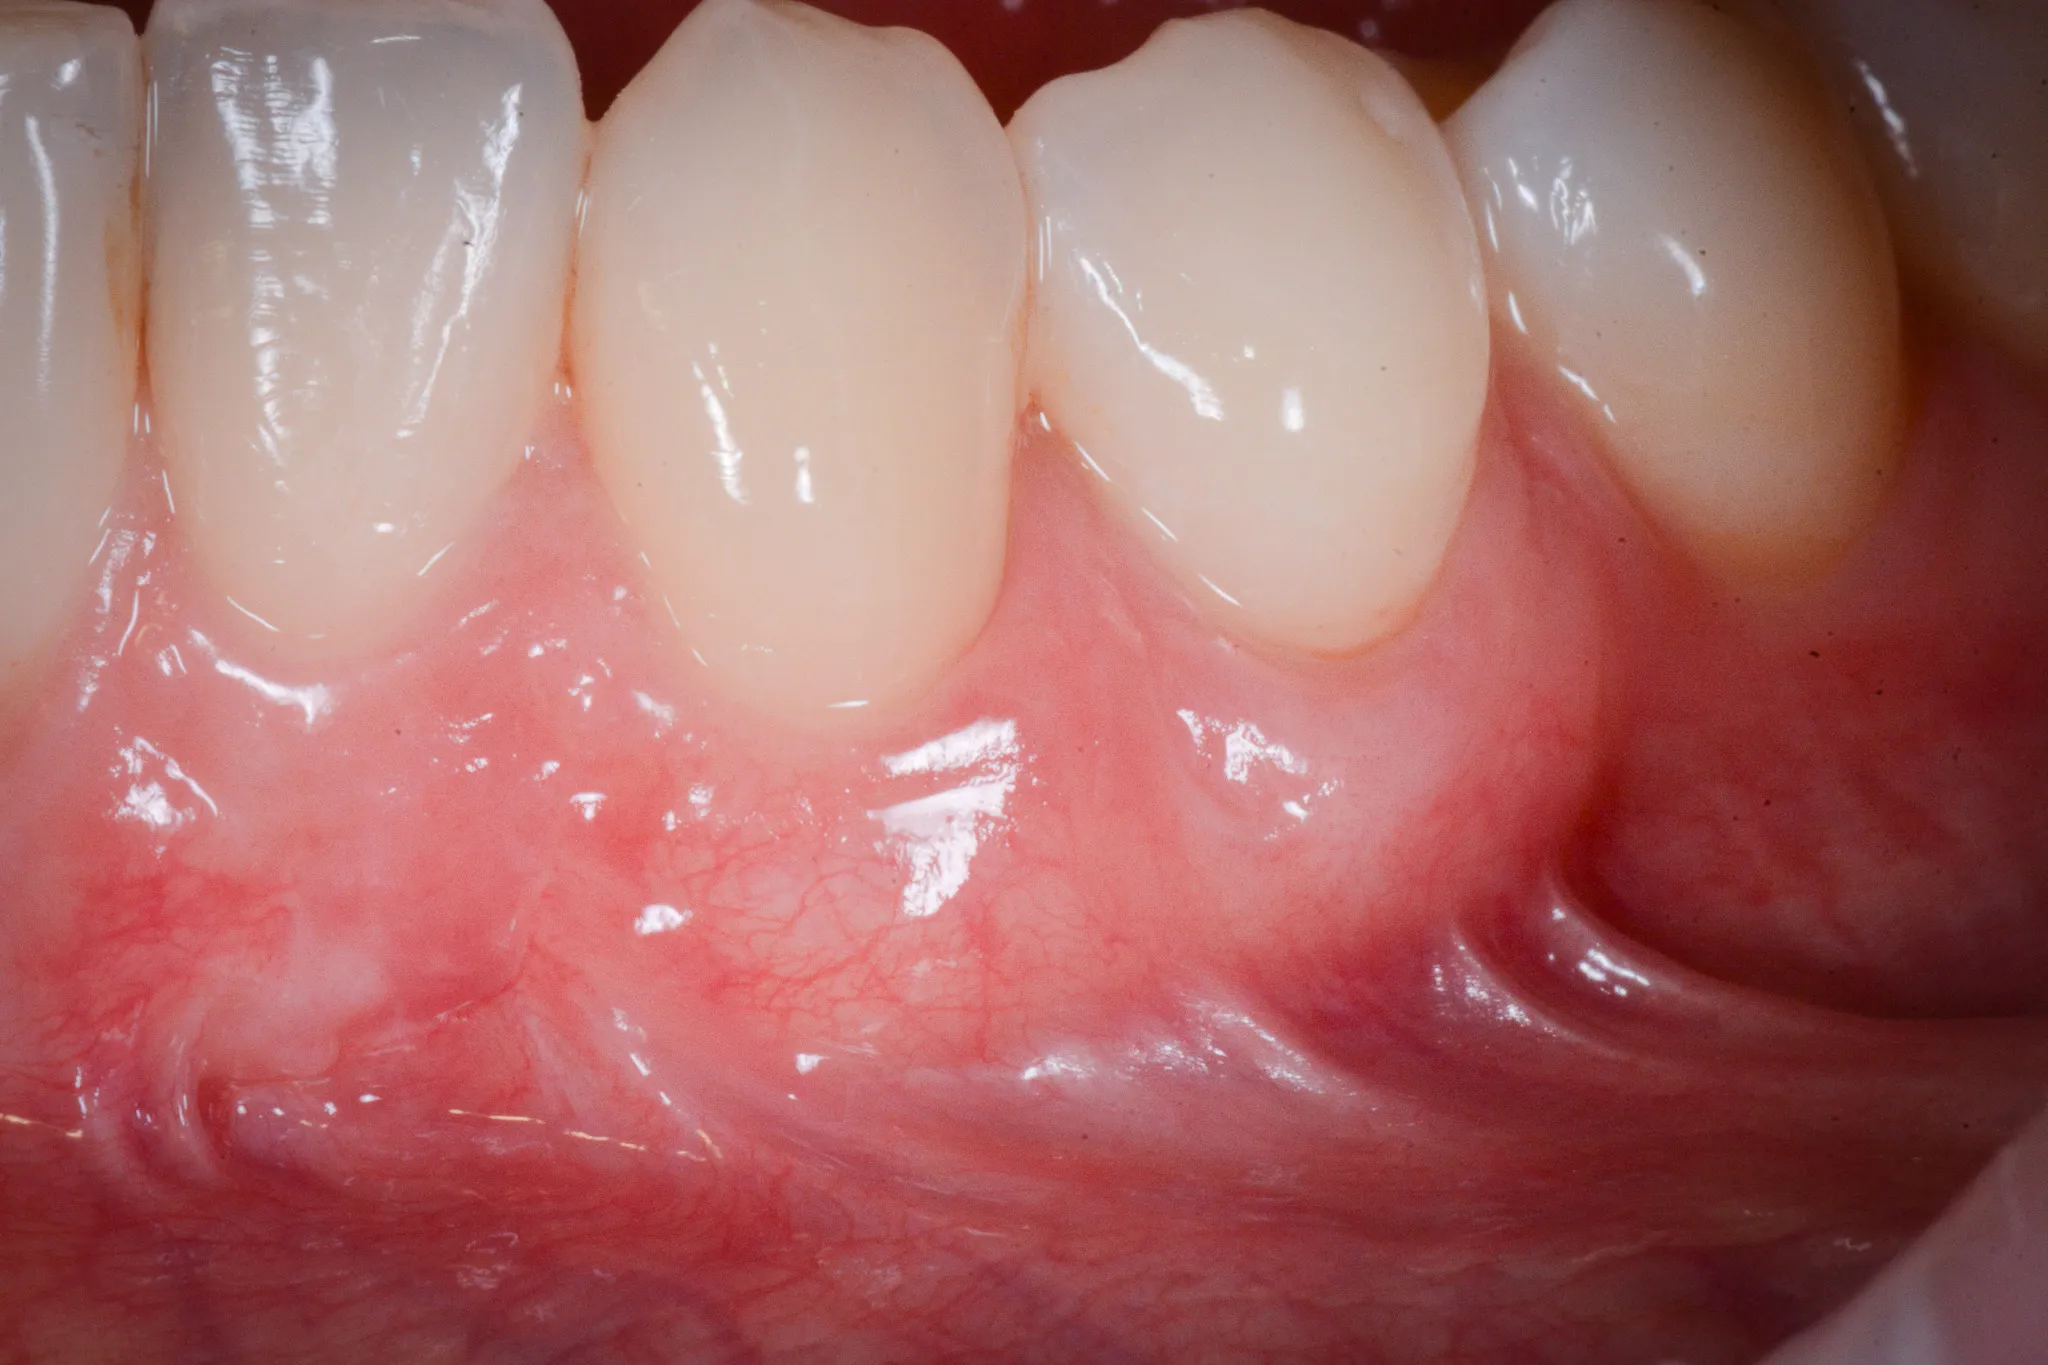

Il tessuto gengivale vero è un tessuto connettivo rivestito da epitelio cheratinizzato (in sostanza, un tessuto più spesso e resistente adeso all’osso sottostante). Quando si ritira, espone la radice del dente — una superficie che non è progettata per stare a contatto con l’ambiente orale. La radice è più porosa dello smalto, più vulnerabile alla carie, più sensibile agli stimoli termici.

Inoltre, a volte la gengiva si assottiglia per vari motivi lasciando spazio da un tessuto più delicato (mucosa orale) che è identico a quello che riveste le guancie e l’interno delle labbra.

Spazzolamento traumatico. Lo spazzolino rigido, usato con movimenti orizzontali e pressione eccessiva, abrade il margine gengivale sottile, soprattutto vestibolare. Il danno è cronico, progressivo, spesso unilaterale — il lato opposto alla mano dominante è quello più colpito.

Biotipo sottile. Alcune persone hanno gengive sottili per costituzione — una banda stretta di cheratinizzata, un periostio esile, una corticale ossea vestibolare ridotta a un velo. In questi pazienti, anche stimoli minimi possono innescare la recessione.

Non tutte le recessioni richiedono un intervento. Alcune sono stabili da anni, non progrediscono, non creano problemi. Il paziente convive con esse senza saperlo.

La progressione è un criterio decisivo. Una recessione che aumenta nel tempo va trattata prima che diventi irrecuperabile.

L’altro criterio molto importante è l’ampiezza del tessuto gengivale. Sotto i due millimetri, è consigliabile intervenire.

L’innesto connettivale sottoepiteliale (SCTG) con lembo coronalmente avanzato (CAF) è il gold standard. La network meta-analisi di Chambrone et al. (2022), pubblicata sul Journal of Periodontology, ha analizzato 38 studi randomizzati su 1.265 recessioni e ha confermato che questa tecnica è la più efficace per copertura radicolare completa, copertura media e guadagno di tessuto cheratinizzato (DOI).

In alcuni casi è necessario ispessire i tessuti, oltreché spostarli per coprire le radici. L’ispessimento si ottiene con un prelievo di tessuto connettivo dal palato o con dei biomateriali chiamati “matrici dermiche”. Il materiale interposto (innesto dal paziente o matrice) fornisce spessore, mentre il lembo spostato in senso coronale protegge e rivascolarizza il sito.